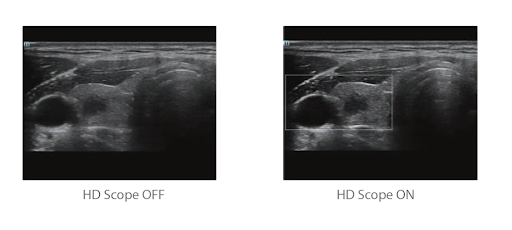

Область HD: более четкое изображение в пределах области интереса

Когерентный пространственный синтез: дальнейшее улучшение качества изображения при пространственном